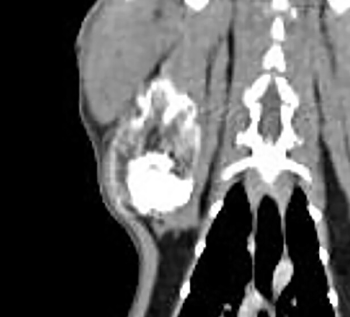

별놈의 지방종, 고양이 견갑골 뼈속부터 지방종?

제목에 딱 박힌 Rare 하다는 말. 그냥 신기한 구경정도로 생각하는게 좋을듯 하다.

양성 종양이지만 뼈를 파괴할 수 있다는 교훈 정도는 기본으로 가지고 가야 할듯 하다.